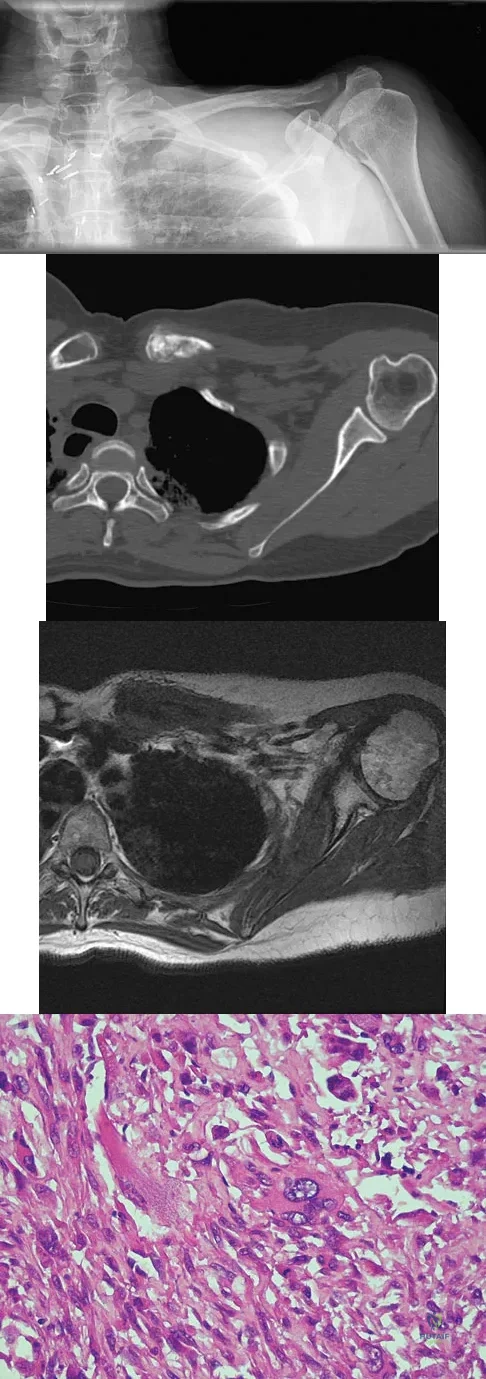

A 47-year-old woman has had left medial clavicle pain for the past 6 months. History is remarkable for mediastinal non-Hodgkin's lymphoma, treated with mantel radiation 22 years ago. A radiograph, CT scan, MRI scan, and a biopsy specimen are shown in Figures 68a through 68d. What is the most likely diagnosis?

Explanation